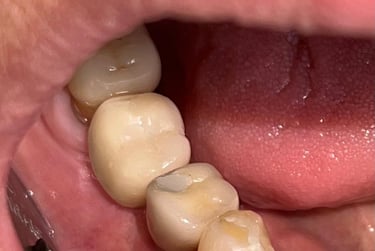

Aspecto Radiográfico Final com Implantes e Coroas

Implantes perdidos por peri implantite - Imagens originais — nenhuma contém retoques

Implante feito por outro profissional há cerca de 5 anos desenvolveu inflamação, saída de pus e gengiva inflamada, indicando peri-implantite, uma infecção que pode comprometer o implante se não tratada.